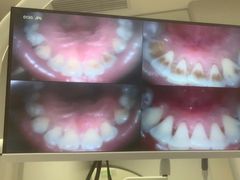

• 德伦口腔(海珠总院)

• -德伦口腔(海珠总院)